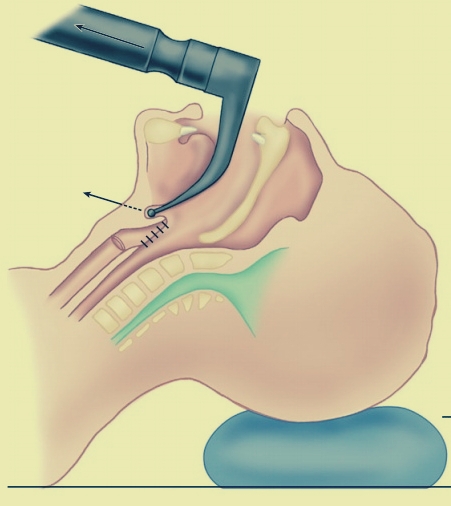

Sellick maneuver – Cricoid pressure

The application of pressure to the cricoid cartilage of the neck and consequently blocking the oesophagus which passes directly behind it.